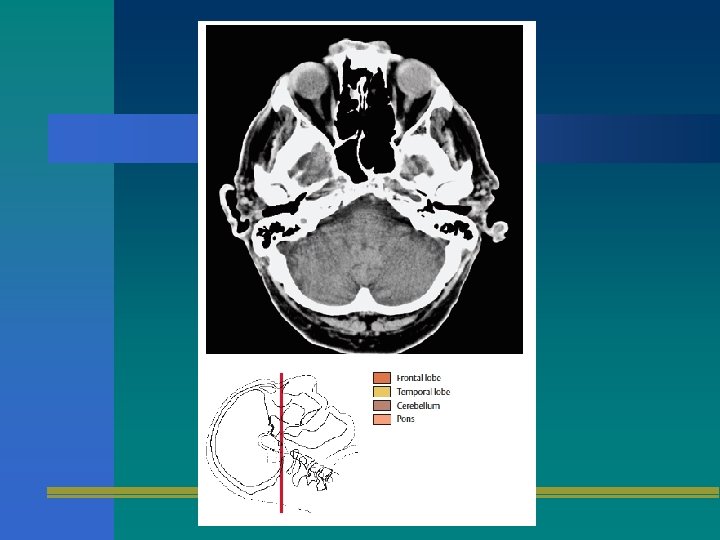

TOMOGRAFIA AXIAL

TAC